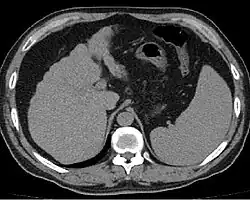

Imaging

Ultrasound is routinely used in the evaluation of cirrhosis.[45] It may show a small and shrunken liver in advanced disease. On ultrasound, there is increased echogenicity with irregular appearing areas.[64] Other suggestive findings are an enlarged caudate lobe, liver surface nodularity[65] widening of the fissures and enlargement of the spleen.[66] An enlarged spleen, which normally measures less than 11–12 cm (4.3–4.7 in) in adults, may suggest underlying portal hypertension.[67] Ultrasound may also screen for hepatocellular carcinoma and portal hypertension.[45] This is done by assessing flow in the hepatic vein.[68] An increased portal vein pulsatility may be seen. However, this may be a sign of elevated right atrial pressure.[69] Portal vein pulsatility is usually measured by a pulsatility index (PI).[68] A number above a certain value indicates cirrhosis (see table below).

Other scans include CT of the abdomen and MRI.[45] A CT scan is non-invasive and may be helpful in the diagnosis.[45] Compared to the ultrasound, CT scans tend to be more expensive. MRI provides excellent evaluation; however, it is expensive.[45]